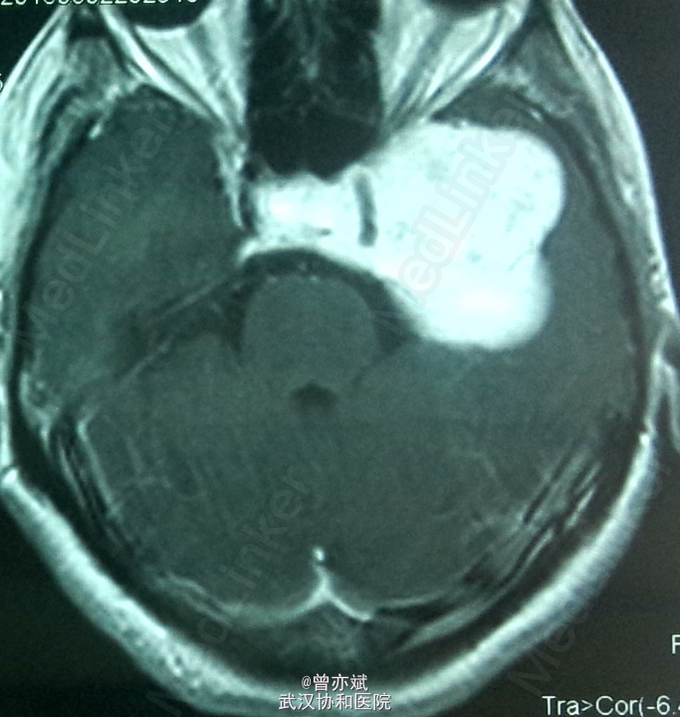

主诉:左眼视力下降十余年 简要现病史:患者10余年前出现左眼视力下降,当时未在意,近期右眼视力下降,行CT提示颅内占位。

查体:左眼视力0.8 颞侧偏盲,右眼视力 0.5 余无明显阳性体征。既往无特殊。 MRI: 稍长 T1,高flair信号,增强明显强化 ,其内点片状强化减低区。诊断:鞍区、中颅窝底巨大占位,考虑脑膜瘤可能性大。

诊断:脑膜瘤?海绵状血管瘤? 处理:手术切除 。

从 MRI上看,矢状位 增强可疑脑膜尾征,增强虽然明显但 不均匀 ,酷似脑膜瘤表现,手术中所见血供丰富,肿瘤实质多为血窦,考虑海绵状血管瘤。如果术前 能 诊断是海绵状血管瘤 ,是开颅手术还是分次伽马刀? 有大神指点一二不?